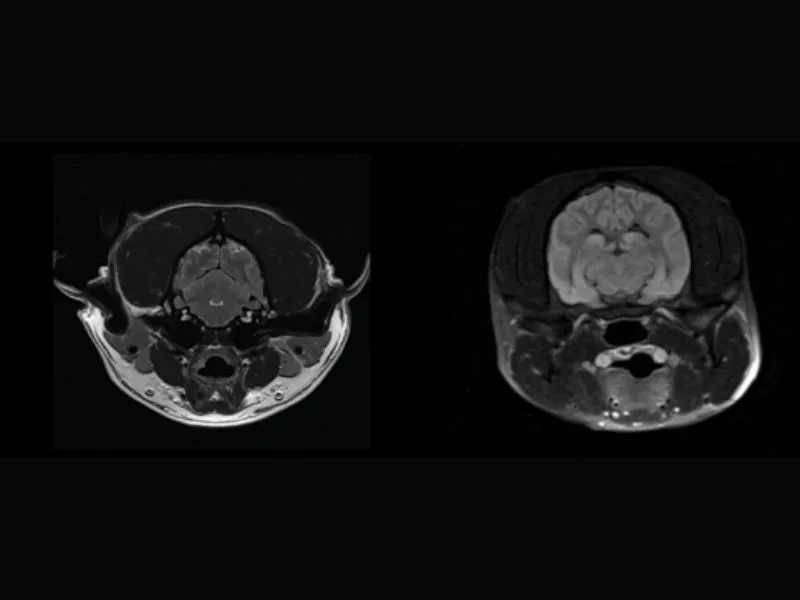

Clinical images

Small animals